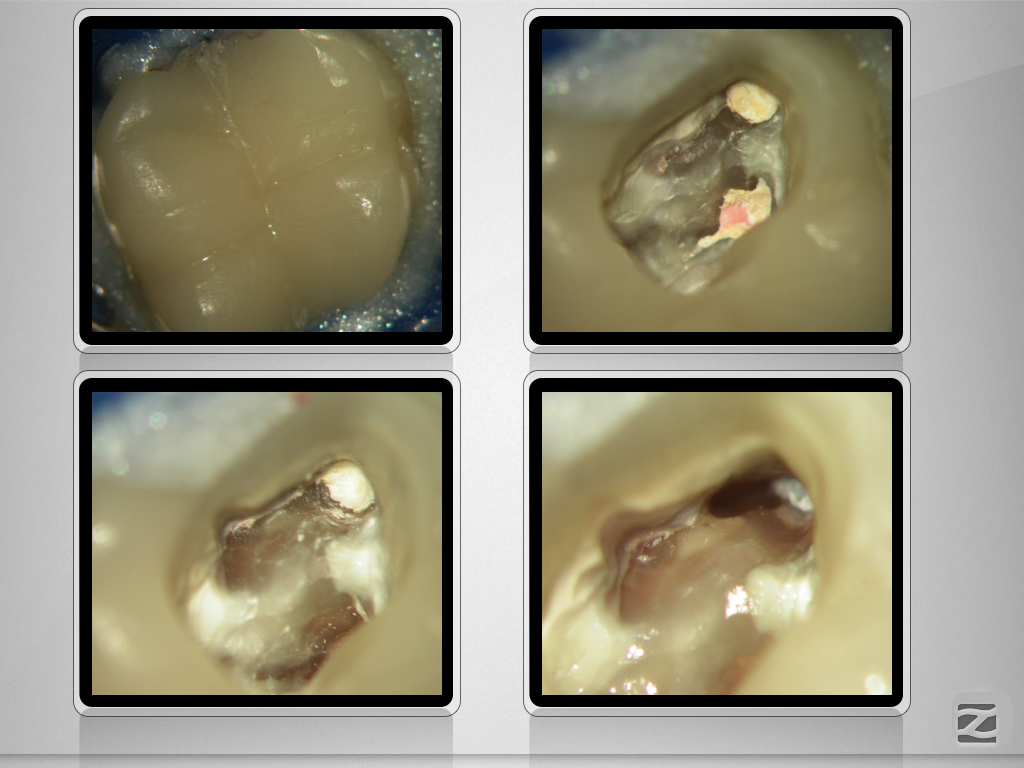

16D.007

1024 × 768

X-Bein/H-förmiger Isthmus/tiefer Split